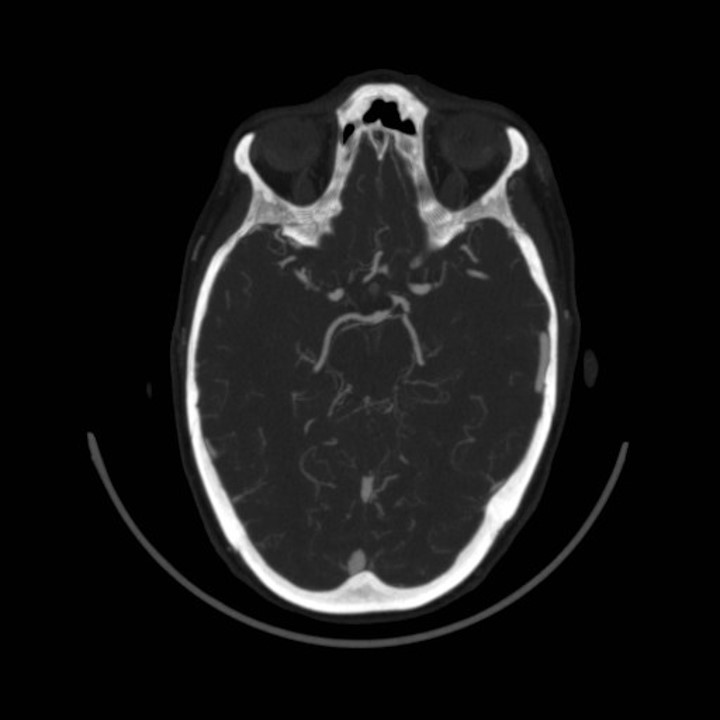

Discussão de tratamento de Fístula Arteriovenosa Dural grau I

Malformações artério venosas durais intracranianas - Discussão de caso fístula dural pós traumática grau I

O principal fator desencadeante do surgimento das FAVDs seria a hipertensão venosa. Condições trombóticas, como trombose do seio venoso, ou não trombóticas, como traumatismo craniano, podem promover restrição ao fluxo sanguíneo no interior do sistema venoso intracraniano, determinando elevação pressórica neste compartimento.  Propuseram que as FAVDs se desenvolvem por conta da abertura de pequenos canais vasculares (microshunts) existentes na dura-máter. Lawton et al ressaltaram que a hipoperfusão cerebral e a isquemia promovem angiogênese, levando ao desenvolvimento de novos shunts arteriovenosos.